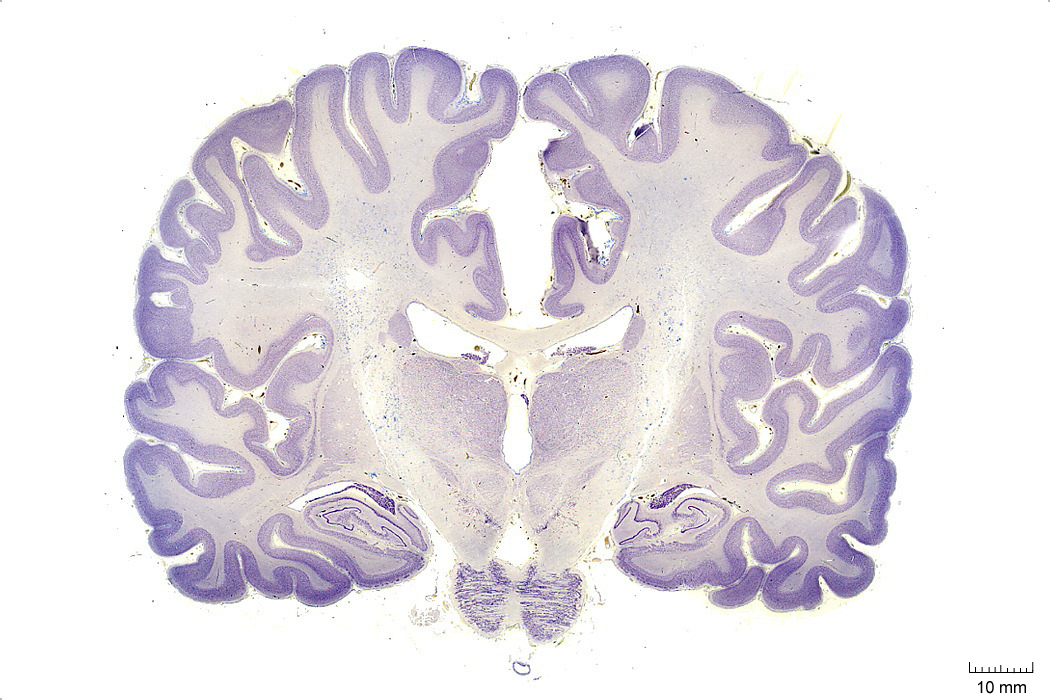

Cell groupings: cortex vs nuclei

Here is one of those cell body violet stained sections-- you can see the cortical sheet and different subcortical nuclei in the thalamus, etc. We will go over this in more detail later.

Cerebellum

Cerebellum is latin for ‘little brain’, and it does have a striking organization with lobes and fissures similar to the folding of the cerebral cortex to increase surface area and packing density of neuronal interconnections. You can see here its main cell body layer, obvious in this purple nissl stain for cell bodies here. It’s in this layer where you will find the beautiful purkinje neurons that we saw images of in lecture 01.